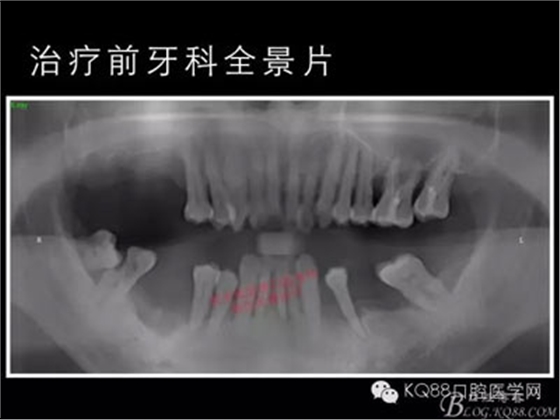

下面的種植病例是為患者提供全口牙齒治療修復(fù)完整過程的下頜部分,我們門診和患者共同配合下目前取得了較好的修復(fù)效果,即將開始的上頜牙齒治療修復(fù)過程仍然艱辛。